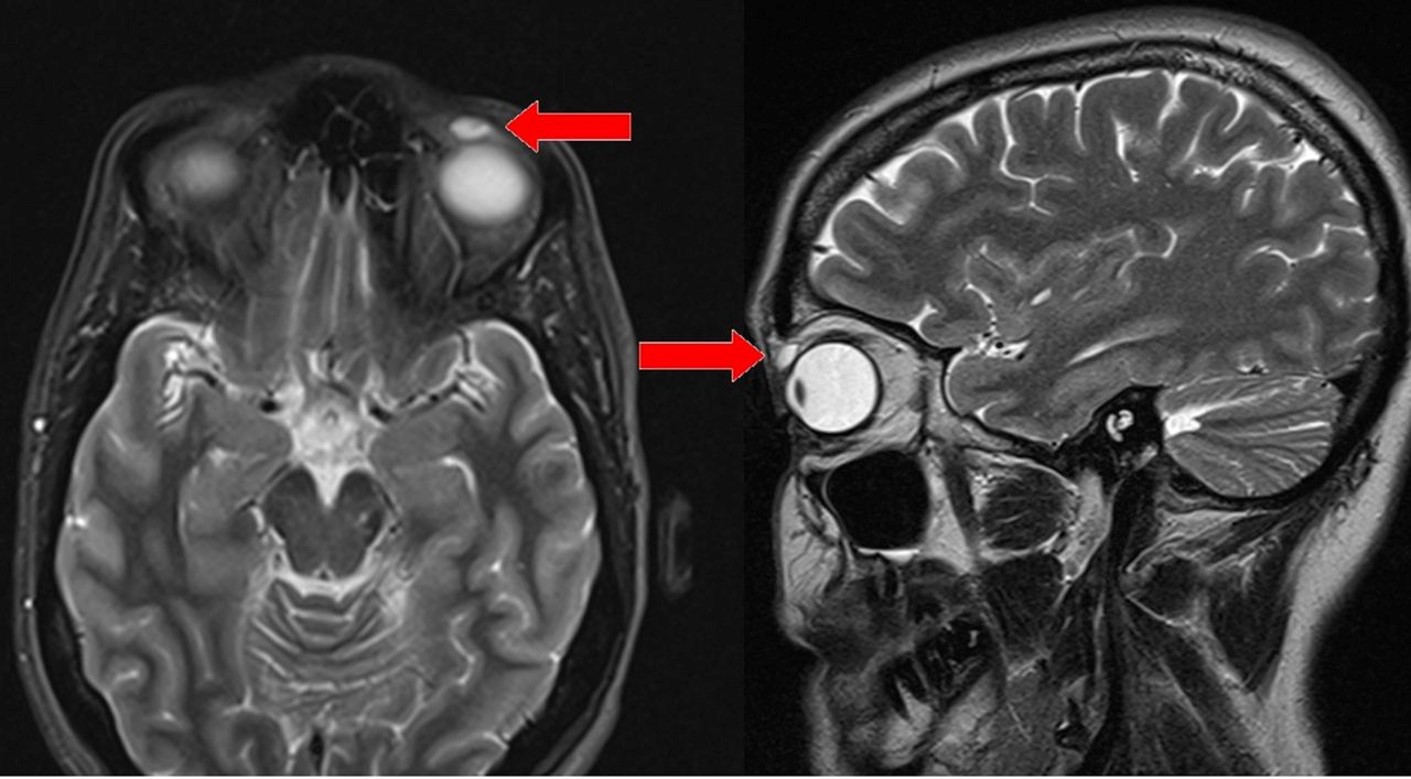

Sau khi thăm khám và chụp MRI, các bác sĩ chuẩn đoán có một khối u nang đường kính 6mm ở trong mắt người phụ nữ này vì vậy họ lên kế hoạch phẫu thuật để loại bỏ nó. Tuy nhiên, đến khi tiến hành mổ mắt bác sĩ mới giật mình thảng thốt vì đó không phải khối u mà là vật thể lạ gì đó. Họ phải hết sức cẩn thận gỡ ra và phát hiện đó chính là một chiếc kính áp tròng.

Lúc này, người phụ nữ cũng thấy hoang mang vì cô khẳng định rằng trong suốt nhiều năm qua cô không hề sử dụng kính áp trong và không hiểu vì sao nó có thể lọt vào mắt cô như vậy. Tuy nhiên, sau đó mẹ của người phụ nữ mới nhớ ra rằng vào năm 14 tuổi, cô thích chơi cầu lông và bị quả cầu bay đập vào mắt. Nhưng khi đó cô nghĩ rằng chiếc kính áp tròng đã rơi ra rồi nên không để ý, ai ngờ cú va đập đó đã khiến chiếc kính ăn sâu vào mắt và yên vị ở đó suốt 28 năm mà chủ nhân không hay biết.